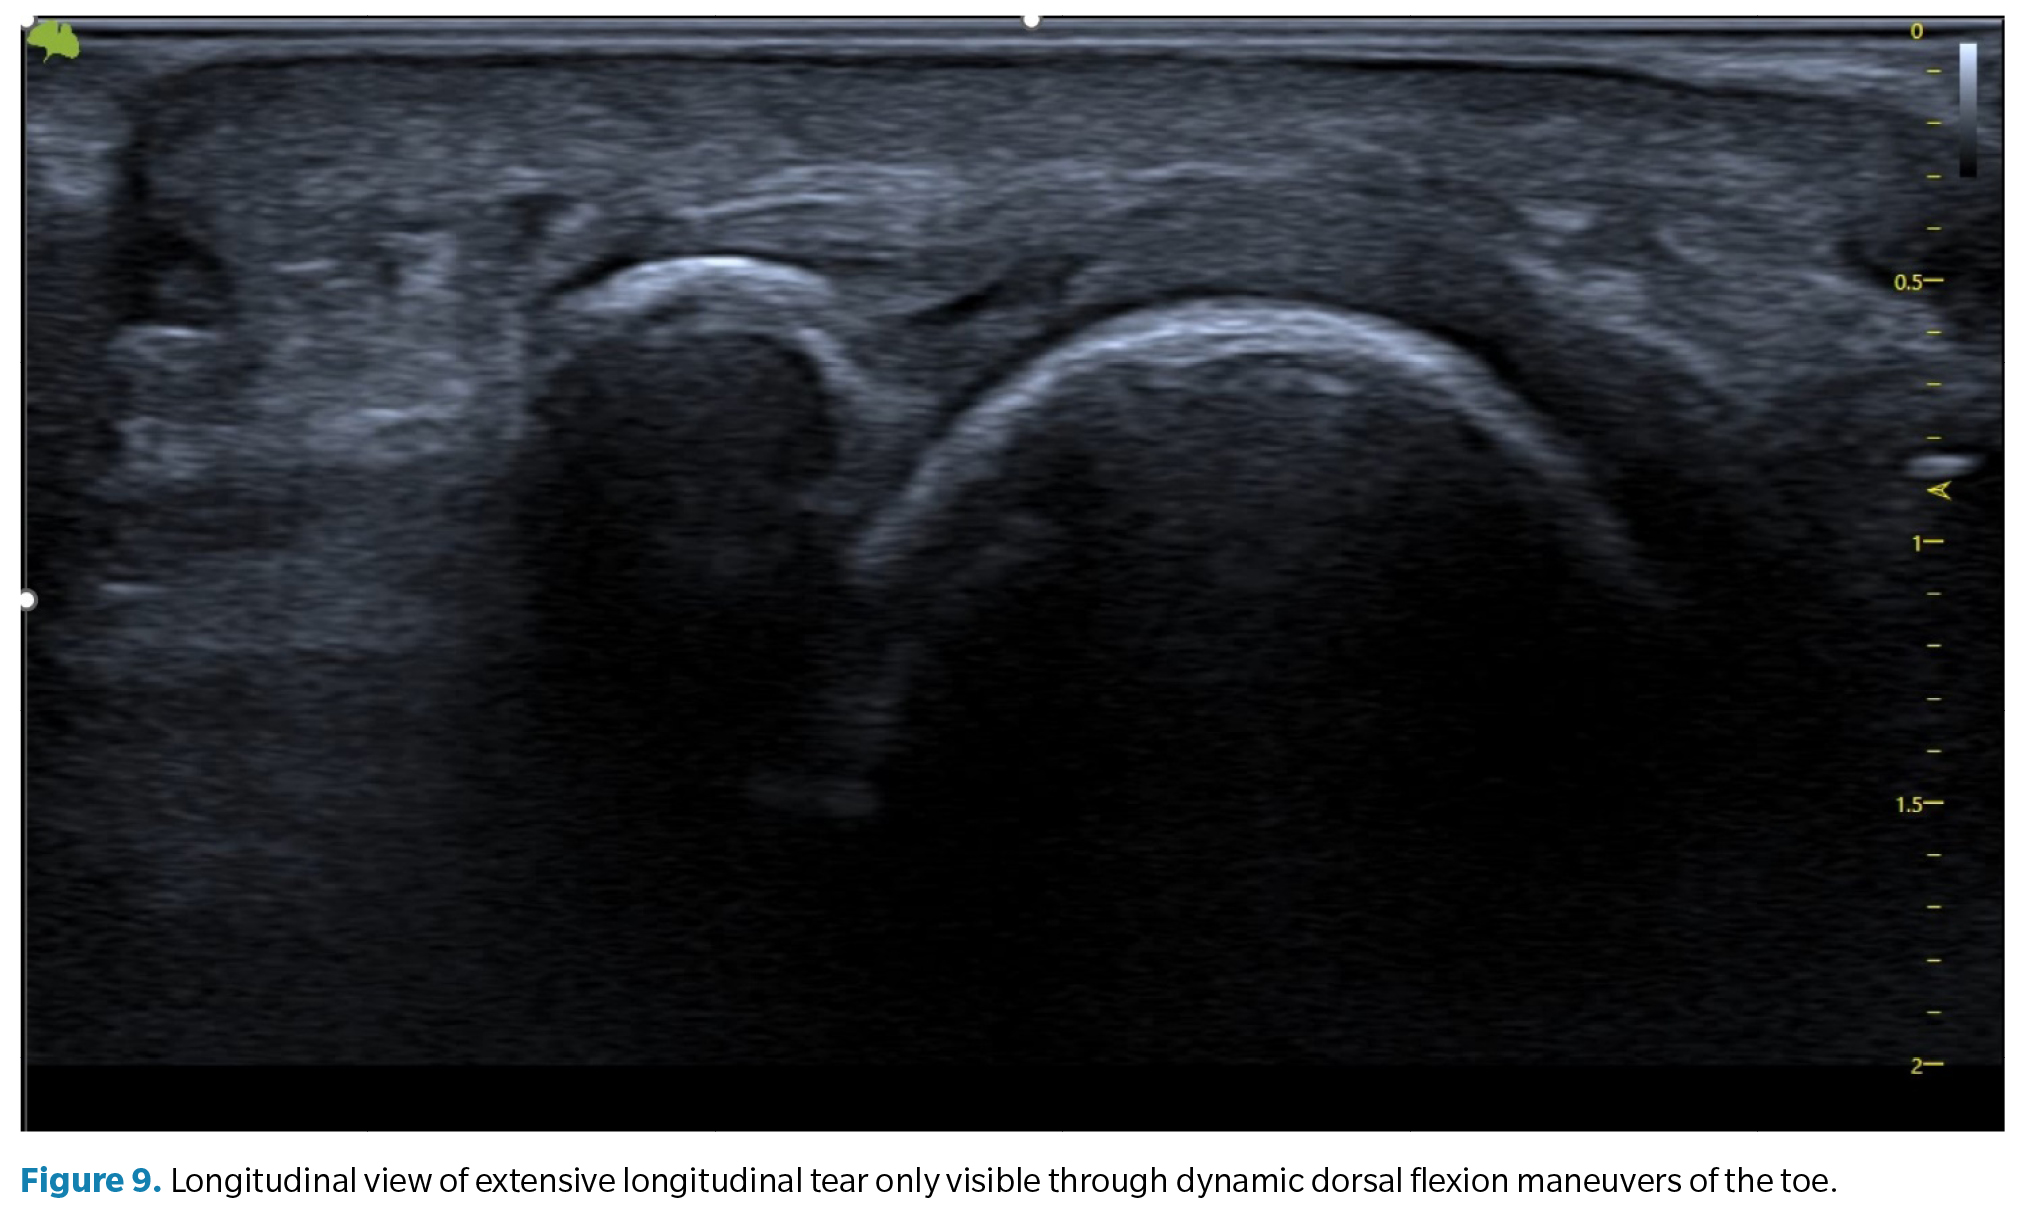

2. Flattening and attenuation of the plantar plate. In these cases, a clear defect is not observed, but attention should be paid when the insertion area, usually thicker, appears thinner than the middle or proximal area of the plate. This generally suggests the presence of a transverse tear extending from the lateral portion to the central portion of the plate(40) (Figure 9).

As mentioned, in all cases, dynamic maneuvers to tense the toe (and the plate) are essential to establish the presence and extent of a tear(41,42). The inability to tense the plate (transition from a curved to a linear state) and the loss of congruent movement between the proximal phalanx and the plate are very suggestive signs of a tear that can only be appreciated with these maneuvers.